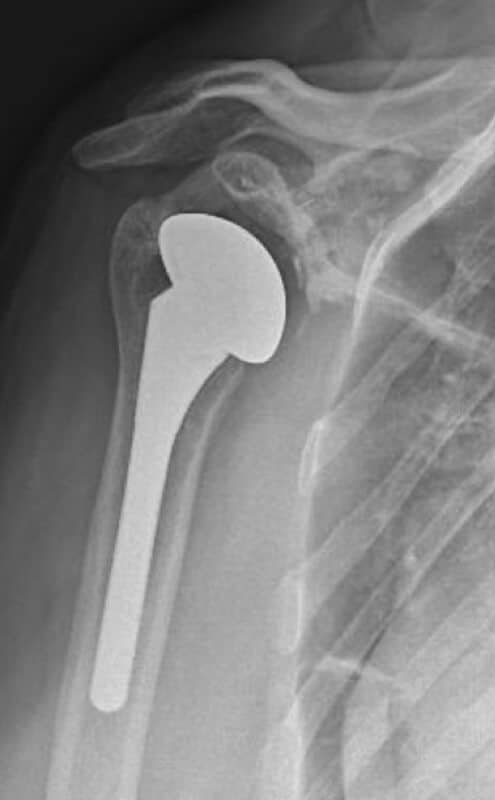

DJO/Enovis, Turon